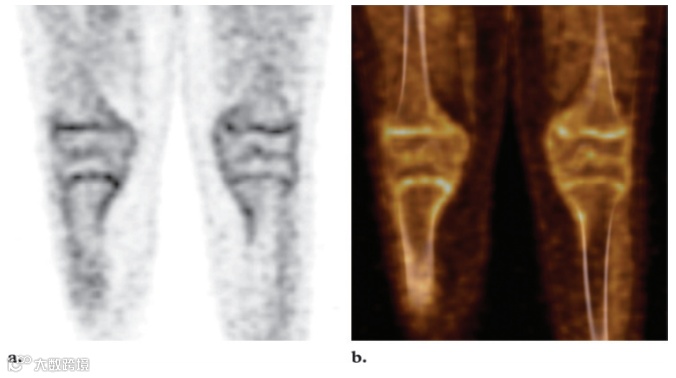

脾脏是免疫系统的重要组成部分,并且具有多种功能,包括清除荚膜细菌、吞噬作用以及产生炎症物质和免疫球蛋白抗体。据推测,脾脏活动的广泛增强反映了脾外感染时该器官的葡萄糖消耗增加。外部放射治疗几个月后,可以观察到骨髓FDG摄取减少。这种现象归因于脂肪组织取代骨髓。通常,正常骨骼中不会发现FDG摄取。然而,骨骼未成熟的儿科患者可能在骨骺和骨突中出现生理线性摄取(图17)。

图17. 冠状FDG PET 扫描 (a) 和融合PET/CT图像 (b) 显示远端股骨和近端胫骨的双侧线性18F FDG摄取,这些发现与长骨骺相对应。